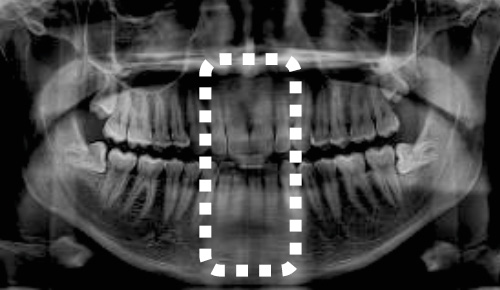

CT撮影では、症例に応じてFOV(Field of View:撮影範囲)を設定します。「Green X 12」では7種類のFOVから診断目的に合わせ最適な選択ができます。

マルチFOVセレクション